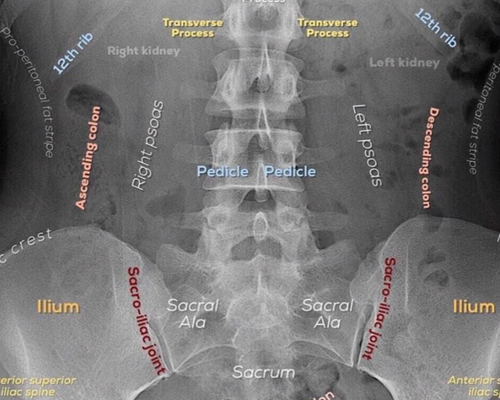

脊柱(背骨)の重要性について脊柱(背骨)は頸椎(7個)、胸椎(12個)、腰椎(5個)、仙骨、尾骨で構成されていて、脊柱のなかには脊柱管がありその中に脊髄神経が通っています。脊柱(背骨)の中の...

骨盤の歪みって何? 骨盤の歪みは身体にどんな影響があるのか?今回は『骨盤の歪み』について簡単に説明したいと思います。 骨盤は身体の要と言われており、上半身と下半身をつなぎ、内臓を...